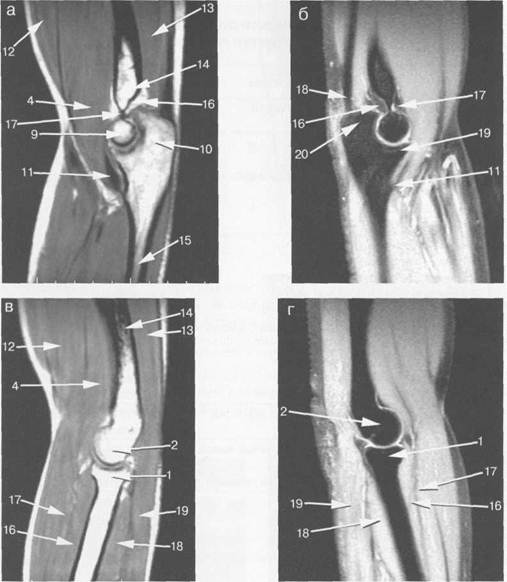

Рис. 19.35. МРТ локтевого сустава. Сагиттальная плоскость.

а: 4 — m. brachialis; 9 — блок плечевой кости; 10 — локтевой отросток локтевой кости; 11 — сухожилие m. brachialis; 12 — т. biceps brachii; 13 — т. triceps brachii; 14 —диафиз плечевой кости; 15 — диафиз лок­тевой кости; 16 — заднее «жировое тело»; 17 — переднее «жировое тело», б — локтевой сустав, сагиттальная плоскость (с подавлением сигнала от жира):

11 — сухожилие m. brachialis; 16 — заднее «жировое тело» (сигнал от жира подавлен); 18 — переднее «жи­ровое тело»; 19 — венечный отросток локтевой кости; 20 — локтевой отросток локтевой кости, в — локтевой сустав, сагиттальная плоскость (через латеральный мыщелок):

1 — головка лучевой кости; 2 — латеральный мыщелок плечевой кости; 4 — m. brachialis; 12 — т. biceps brachii; 13 — т. triceps brachii; 14 — диафиз плечевой кости; 16 — m. extensor digitorum; 17 — т. brachio-radialis; 18 — т. extensor carpi ulnaris; 19 — т. anconeus. r — MPT локтевого сустава, сагиттальная плоскость:

1 — головка лучевой кости; 2 — латеральный мыщелок плечевой кости; 16 — m. extensor digitorum; 17 — т. brachioradialis; 18 — т. extensor carpi ulnaris; 19 — т. anconeus.